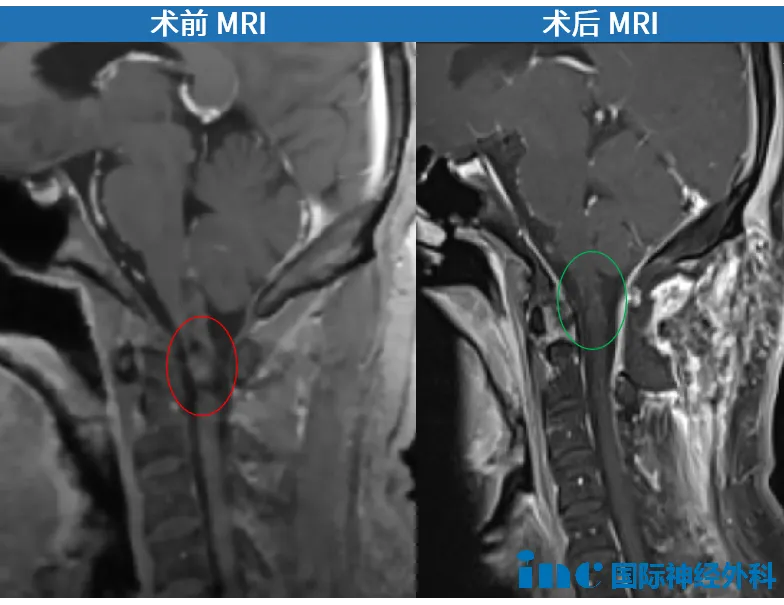

转机出现在病友群分享的INC巴特朗菲教授来华消息。教授分析影像后指出:"C1颈髓内海绵状血管畸形导致内生性出血并延伸至延髓下部,手术切除技术可行。虽非急诊手术,但为预防再出血应尽早干预。"他同时说明此前出血已造成神经损伤,术后症状可能改善但不完全消失。

2024年10月2日巴教授主刀手术,中国团队配合,手术顺利完成。术后首日患者转出ICU,部分功能改善。一年后郑先生恢复正常生活,可进行健身运动。